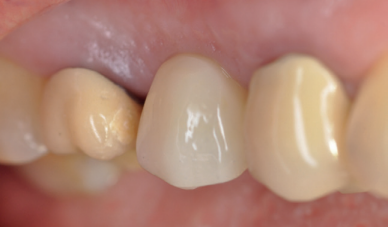

Caso clínico: se presenta el caso clínico de una mujer de 61 años, que acudió a consulta presentando dolor intenso en la zona del segundo premolar superior derecho (1.5). Se realizó la exodoncia del 1.5, usándose como diente donante para realizar una preservación del alveolo tras la extracción. Cuatro meses tras el procedimiento, se colocó un implante y se tomó una biopsia para realizar un análisis histomorfométrico. Un año tras la carga del implante se observaron buenos resultados clínicos y radiográficos.

Clinical case: a 61-year-old woman is presented, who came to private dental clinic presenting intense pain in the area of an upper bicuspid of the first quadrant (1.5). Exodontia of the 1.5 was performed, using it as a donor tooth to obtain the biomaterial to preserve its alveolus. After 4 months re-entry was performed and an implant was placed, harvesting a bone biopsy for histomorphometric analysis. One year post-loading, good clinical and radiographic results were shown.